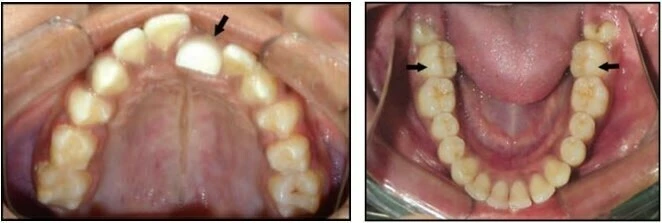

2.3 SAI KHỚP CẮN THEO MẶT PHẲNG NGANG

Trường hợp này bao gồm nhiều kiểu cắn chéo khác nhau. Thông thường các răng hàm trên nằm về phía ngoài so với các răng hàm dưới, nhưng đôi khi do cung răng hẹp hoặc vì một số lý do khác mà tương quan này bị xáo trộn. Chẳng hạn một hoặc nhiều răng hàm trên nằm về phía trong so với các răng hàm dưới, tình trạng này khác nhau về mức độ, vị trí và số lượng răng liên quan.